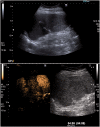

Figure 6.

Large B cell lymphoma. (a) Incidental finding of a large echo-poor mass within the spleen. (b) Early-phase CEUS shows some enhancement predominantly within the periphery of the mass. (c) Late-phase CEUS shows that the bubbles have washed-out and the mass is almost completely unenhanced. In view of the malignant appearances a biopsy was performed showing large B cell lymphoma. (d) PET CT scan demonstrates that the lesion is intensely metabolically active and was shown to be the only site of disease.